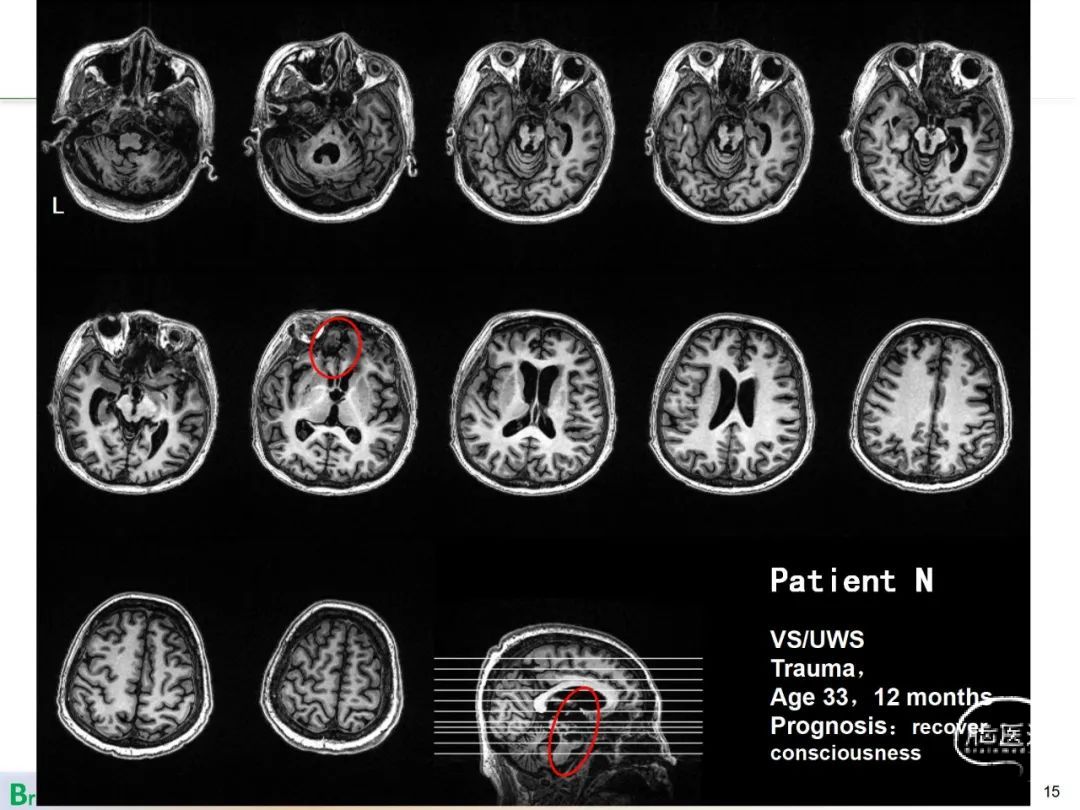

该模型在测试集中能够准确将原诊断为Vs但预后恢复意识的患者辨识出来 ,正确率达到了90%。本研究模型相比较之前报道的研究 ,在样本数量、准确率以及验证方法上都具有明显改进。通过分析预测数学模型中参数的权重,分析了不同预测因素对预测结果的重要程度。发现脑中线功能连接对预测结果起到重要作用, 尤其是执行控制网络与默认网络之间的负功能连接对预后预测有着重要价值,这提示了脑功能网络不同脑区和功能连接与意识障碍预后的关联性 ,为理解意识障碍疾病的神经机制提供了新线索。

中国科学院自动化研究所模式识别国家重点实验室和脑网络组研究中心 ,联合陆军总医院和广州总医院组成联合攻关团队。在基于病因、年龄和病程作为重要预测指标的基础上,使用基于脑功能磁共振成像(fMRI)的患者脑功能网络特征,结合机器学习相关算法,研究出了一个能预测患者1年之后是否恢复意识的计算模型 , 准确率达到了88%:更 为重要的是已成功预测了多例临床医生最初判定恢复无望而最终恢复意识的患者。